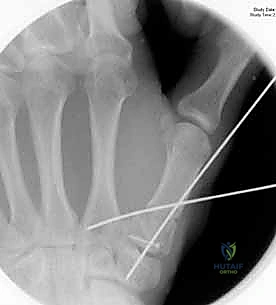

1. الرد المغلق والتثبيت عبر الجلد بالإبر (CRPP - Closed Reduction and Percutaneous Pinning)

هذا الإجراء هو الخيار المفضل لكسور "بينيت" التي يمكن إعادتها لمكانها بدون فتح جراحي كبير.

* الخطوات: يتم إجراء العملية تحت التخدير الموضعي أو الكلي. باستخدام جهاز الأشعة السينية المباشر في غرفة العمليات (C-arm Fluoroscopy)، يقوم البروفيسور هطيف برد الكسر إلى مكانه المثالي.

* بعد ذلك، يتم إدخال إبر معدنية دقيقة (K-wires أو Kirschner wires) عبر الجلد مباشرة لتثبيت قاعدة المشط الأول بالعظم المربعي، وأحياناً بالمشط الثاني لزيادة الاستقرار.

* الميزة: شقوق صغيرة جداً، ألم أقل، وشفاء أسرع. يتم إزالة هذه الإبر عادة في العيادة بعد 4 إلى 6 أسابيع.